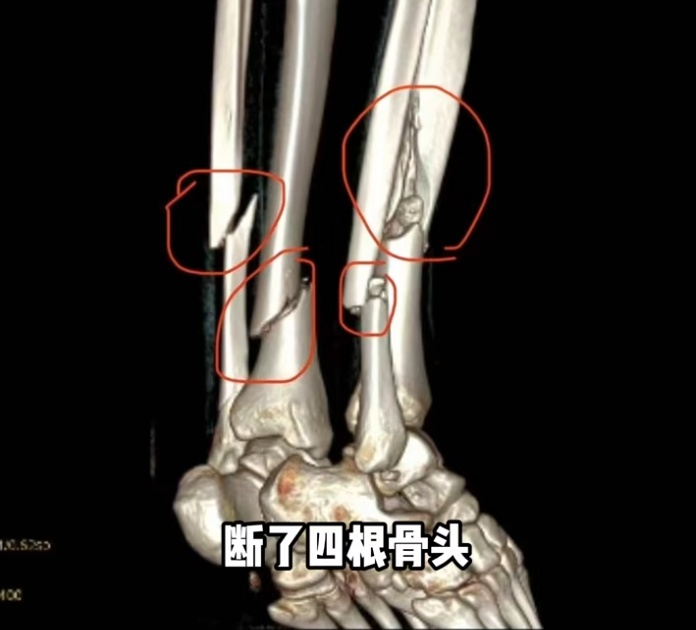

据她2月27日发布的动态,她在新疆滑雪时摔倒,断了4根骨头,右腿胫骨粉碎性骨折,处理伤口的时候,她痛苦喊叫声响彻诊室。

据她描述,轻微的活动都能感受到碎骨扎进肉里,不敢想象有多疼。

千一称在新疆接受手术,左腿2块钢板16颗钉子,右腿2条髓内钉和6颗固定钉子,缝了45针。